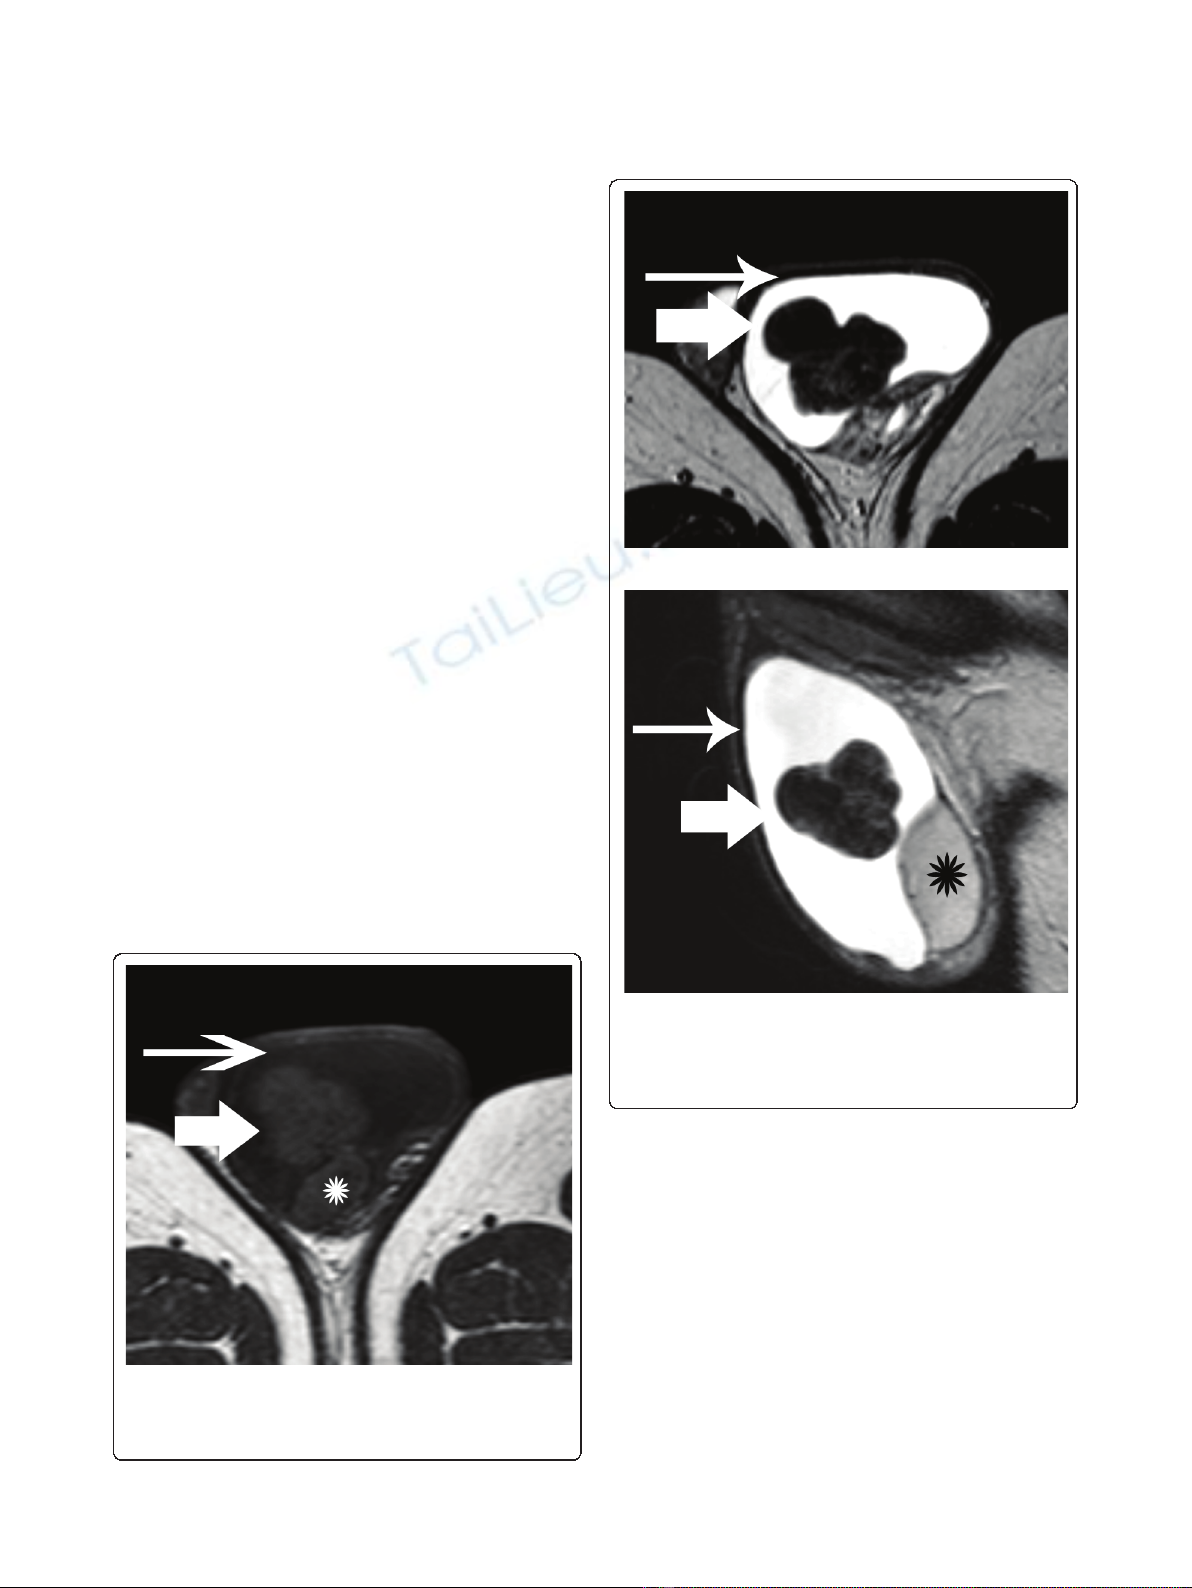

. A multilobular left paratesticular mass (Fig-

ures 1, 2, 3), in close proximity to the testicular tunicae

of the superoanterior aspect of his left testis was

detected. The dimensions of the tumor were 33 × 34 ×

32 mm. T1-weighted images demonstrated a mass isoin-

tense to his testicular parenchyma (Figure 1). The mass

Figure 1 Transverse T1-weighted image depicts a multilobular

left scrotal mass (arrow), located in the paratesticular space.

The lesion had similar signal intensity, when compared to the

normal testicular parenchyma (asterisk). Left hydrocele (long arrow).

Figure 2 T2-weighted images (a) Transverse and (b) sagittal

T2-weighted images show tumor heterogeneity. The mass

(arrow) was mainly hypointense on T2-weighted images, a finding

suggestive of the presence of fibrous tissue. Left hydrocele (long

arrow). Normal left testis (asterisk).

MR examination of the scrotum in our patient

revealed the presence of a sharply-demarcated

multilobular paratesticular mass, isointense on T1-

weighted images, heterogeneous, but predominantly of

very low signal intensity on T2-weighted images. One